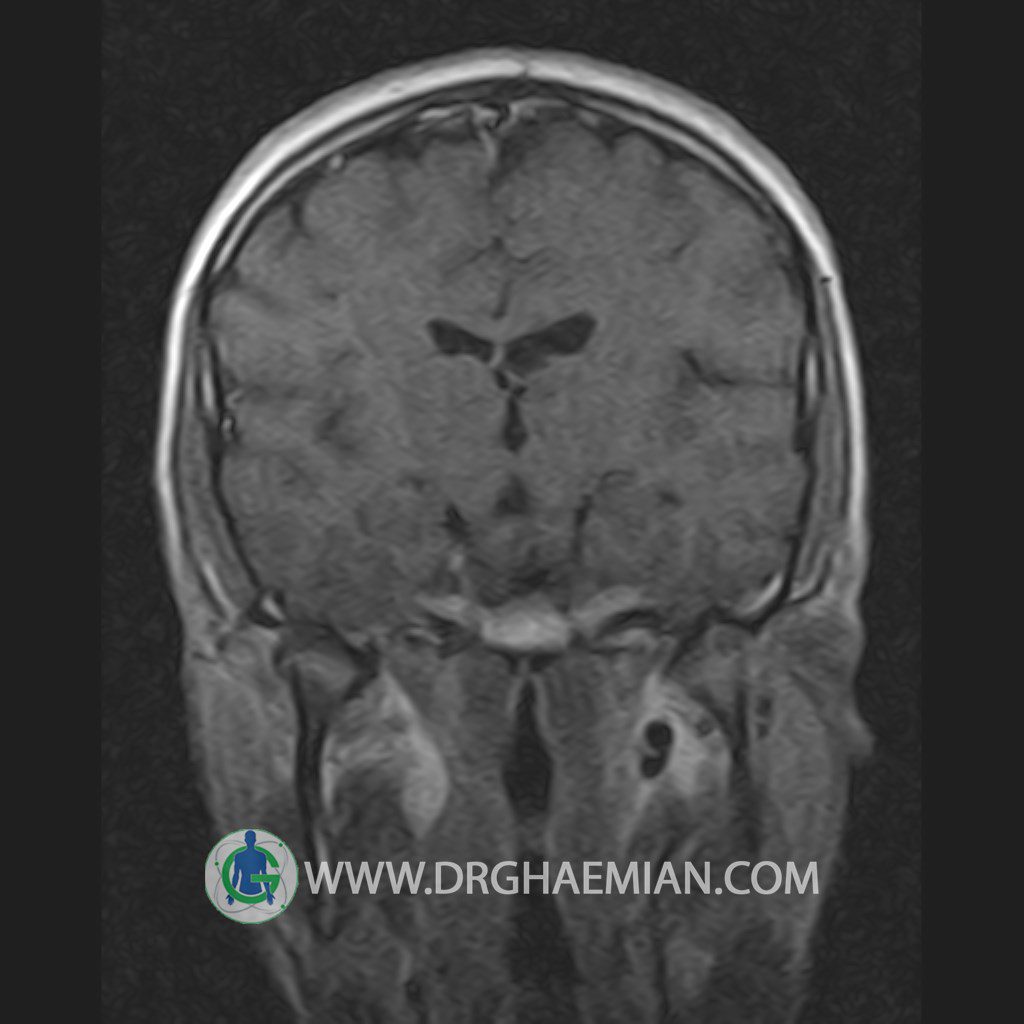

پزشکان اغلب از تصویربرداری ام آر آی برای تشخیص و درمان عارضه های پزشکی که فقط با استفاده از اشعه ایکس یا میدان مغناطیسی و امواج رادیویی قابل مشاهده است، استفاده می کنند. دستگاه ام آر آی تصاویر دقیق از ساختار های داخلی بدن ایجاد می کند. در این کیس یک میکروآدنوم در هیپوفیز بیمار مشاهده می شود.

HYPOPHYSIS MRI

(with and without contrast)

Technique: Axial , coronal T1 , Axial , coronal , sagittal T2 , Axial, coronal T1 post Gd & 64 dynamic thin coronal slices.

The infundibulum is centered and of normal size .

The optic chiasm and suprasellar spaces appear normal .

The cavernous sinus and imaged portions of the internal carotid artery and carotid siphon are unremarkable .

– Small hypoenhancing mass lesion ( 3 x 4 mm ) in posterior of pituitary stalk suggestive for micro adenoma